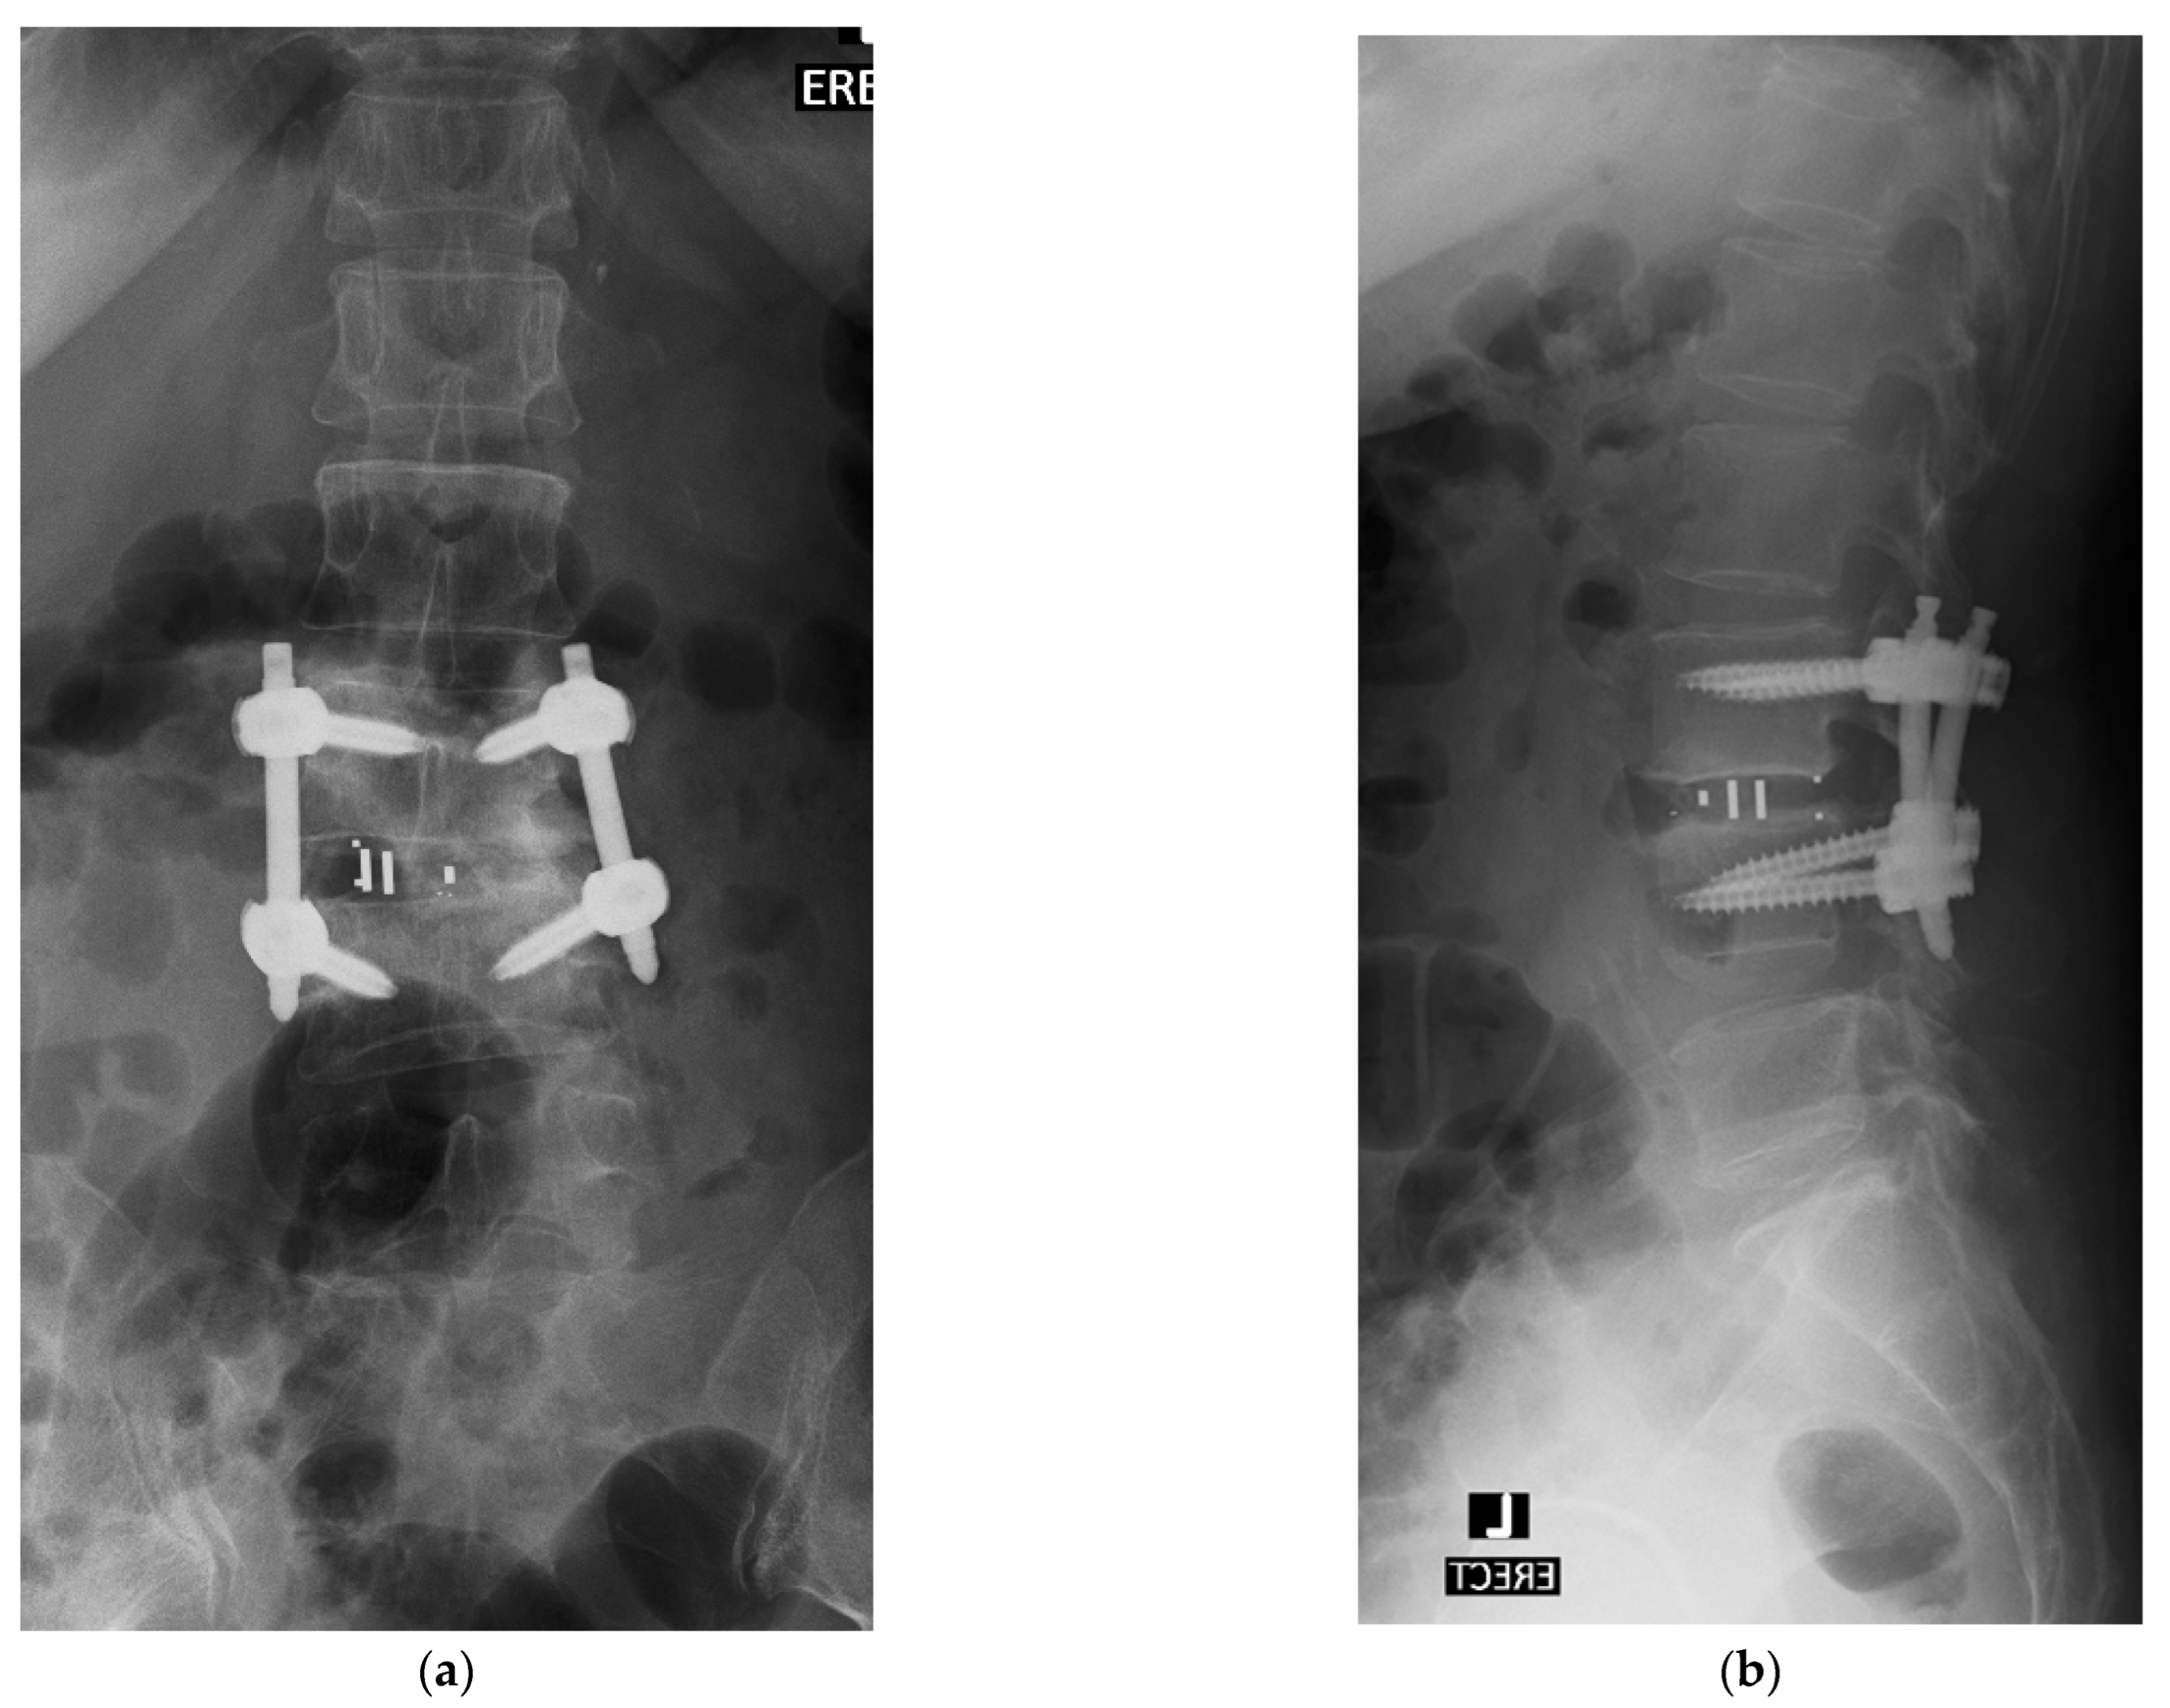

4.1. Case 1: Madam M

4.2. Case 2: Madam R

4.3. Case 3: Madam M